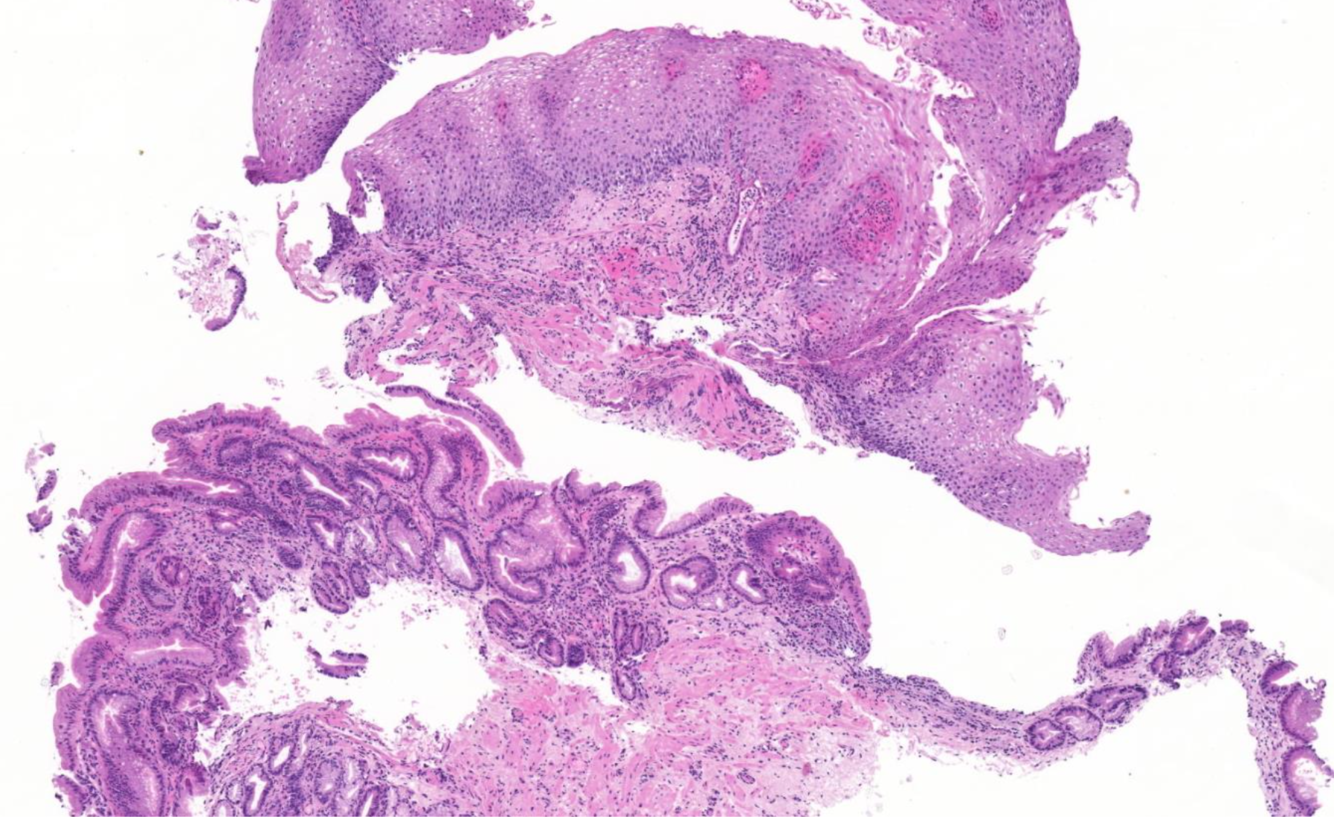

Diagnose?

Barettmetaplasie mit Dysplasie

-> Erkennt man an Becherzellen